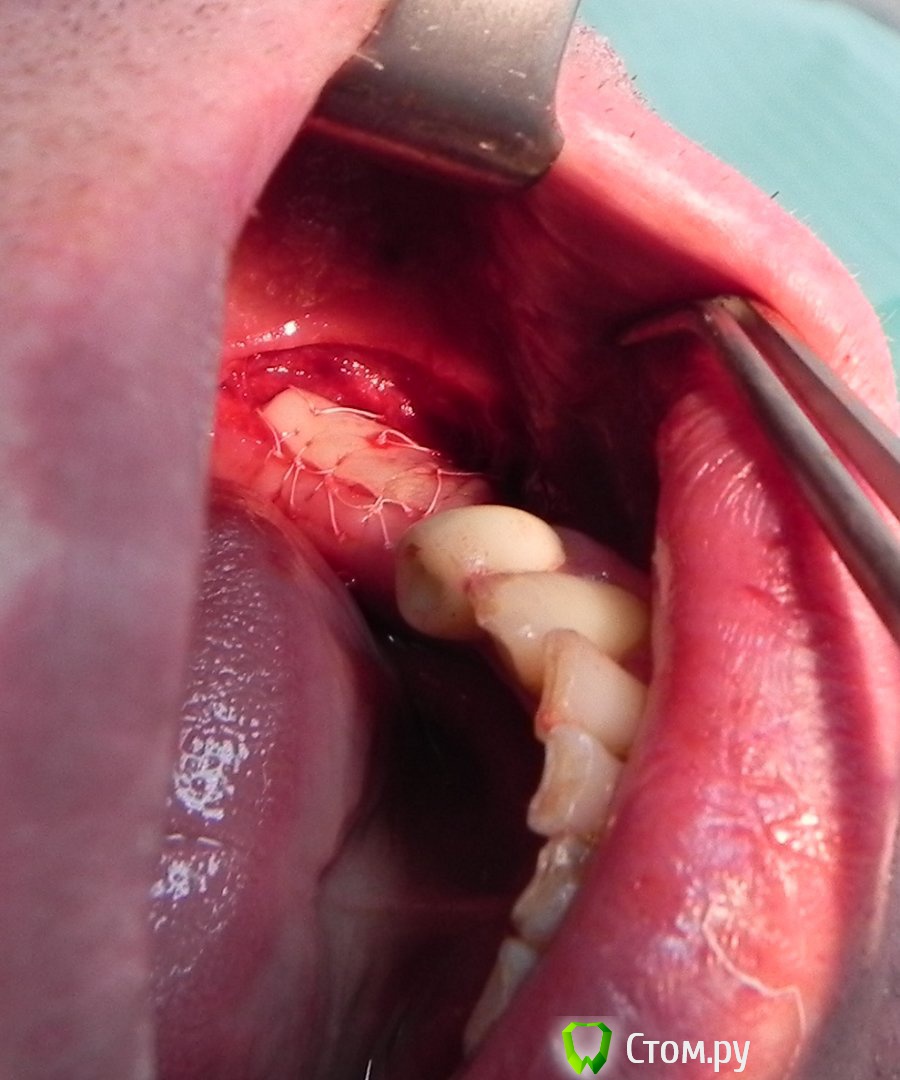

Kostoprav Опубликовано 12 июня, 2014 Поделиться Опубликовано 12 июня, 2014 Как-то наткнулся на одно видео в сети, снятое с курса г-жи Февралевой на iPAD, так там она учит подшивать по краям и пару в центре! ))Все течет, все меняется! я тоже так делаю, никаких некрозов Ссылка на комментарий

АнтонТЛТ Опубликовано 13 июня, 2014 Поделиться Опубликовано 13 июня, 2014 доктора не оставьте без внимания и еще-в случае кейса тс лоскут деэпителизировать не имеет смысла?Лучше в конверт под расщепленный, питание трансплантата будет с двух сторон. В случае тс деэпителизировать нет смысла. Ссылка на комментарий

geguli4 Опубликовано 15 июня, 2014 Поделиться Опубликовано 15 июня, 2014 Ромик,молодец.Естественно так уже почти никто не делает.Я бы тоже положил в конверт...И по цвету более походило бы Ссылка на комментарий

Doctorstomlis Опубликовано 16 июня, 2014 Поделиться Опубликовано 16 июня, 2014 Как-то наткнулся на одно видео в сети, снятое с курса г-жи Февралевой на iPAD, так там она учит подшивать по краям и пару в центре! ))Все течет, все меняется!Просто существует 2 метода пришивания лоскута :с растягивающими швами и микрохирургические швы. Ссылка на комментарий